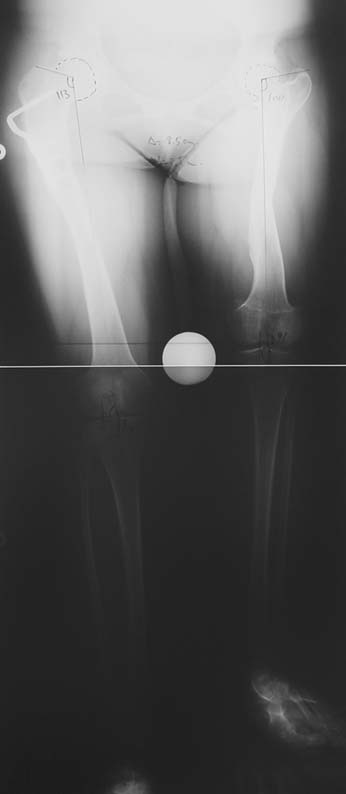

Many patients don’t want to use a shoe support thicker than 2 cm. For length differences between 2 cm and 5 cm, shortening may be considered for tall patients. This can be performed in growing children with a small, minimally invasive, uncomplicated procedure called epiphysiodesis. This means surgical disruption of one or more growth plates. There is a growth plate at the ends of femur, tibia and fibula; this procedure does not halt all growing of the leg. The growing of the longer leg is calculated and halted to allow the shorter leg to catch up.If the procedure is performed at a too early or too late age, the correction may be too much or too little, respectively. Hence, it is important to accurately calculate the most appropriate age for epiphysiodesis. When and at which bone segment epiphysiodesis will be performed shall be calculated by the doctor using different methods such as Gren-Anderson diagram, Moseley curve or Paley’s multiplier method.Epiphysiodesis is not an option for adults because growth plates ar closed. In adults, a bone segment has to be excised surgically in order to shorten the leg. This is usually performed at femur and bone is later fixed with an intramedullary nail. The biggest advantage of this system is that it acutely provides limb length equality for discrepancies less than 5 cm. The common disadvantage of epiphysiodesis and shortening is the shortening of total height of the patient. Because we don’t advice shortening more than 5 cm, height loss can’t be more than 5 cm. For patients who don’t want an epiphysiodesis or shortening operation for length inequalities less than 5 cm, limb lengthening can be preferred in order to equalize the length difference.This can be combined with epiphysiodesis and shortening to decrease a need for another lengthening operation or to decrease the lengthening amount required.

3. POSTTRAUMATIC LOWER LIMB SHORTNESS (MALUNION)

This type of shortness occurs after a fracture heals in a shortened position. Most cases are seen in adults and can be treated with one lengthening operation. Additional deformities can be corrected simultaneously. Most of these cases can be treated with lengthening over nail or just corrections and intramedullary nailing.